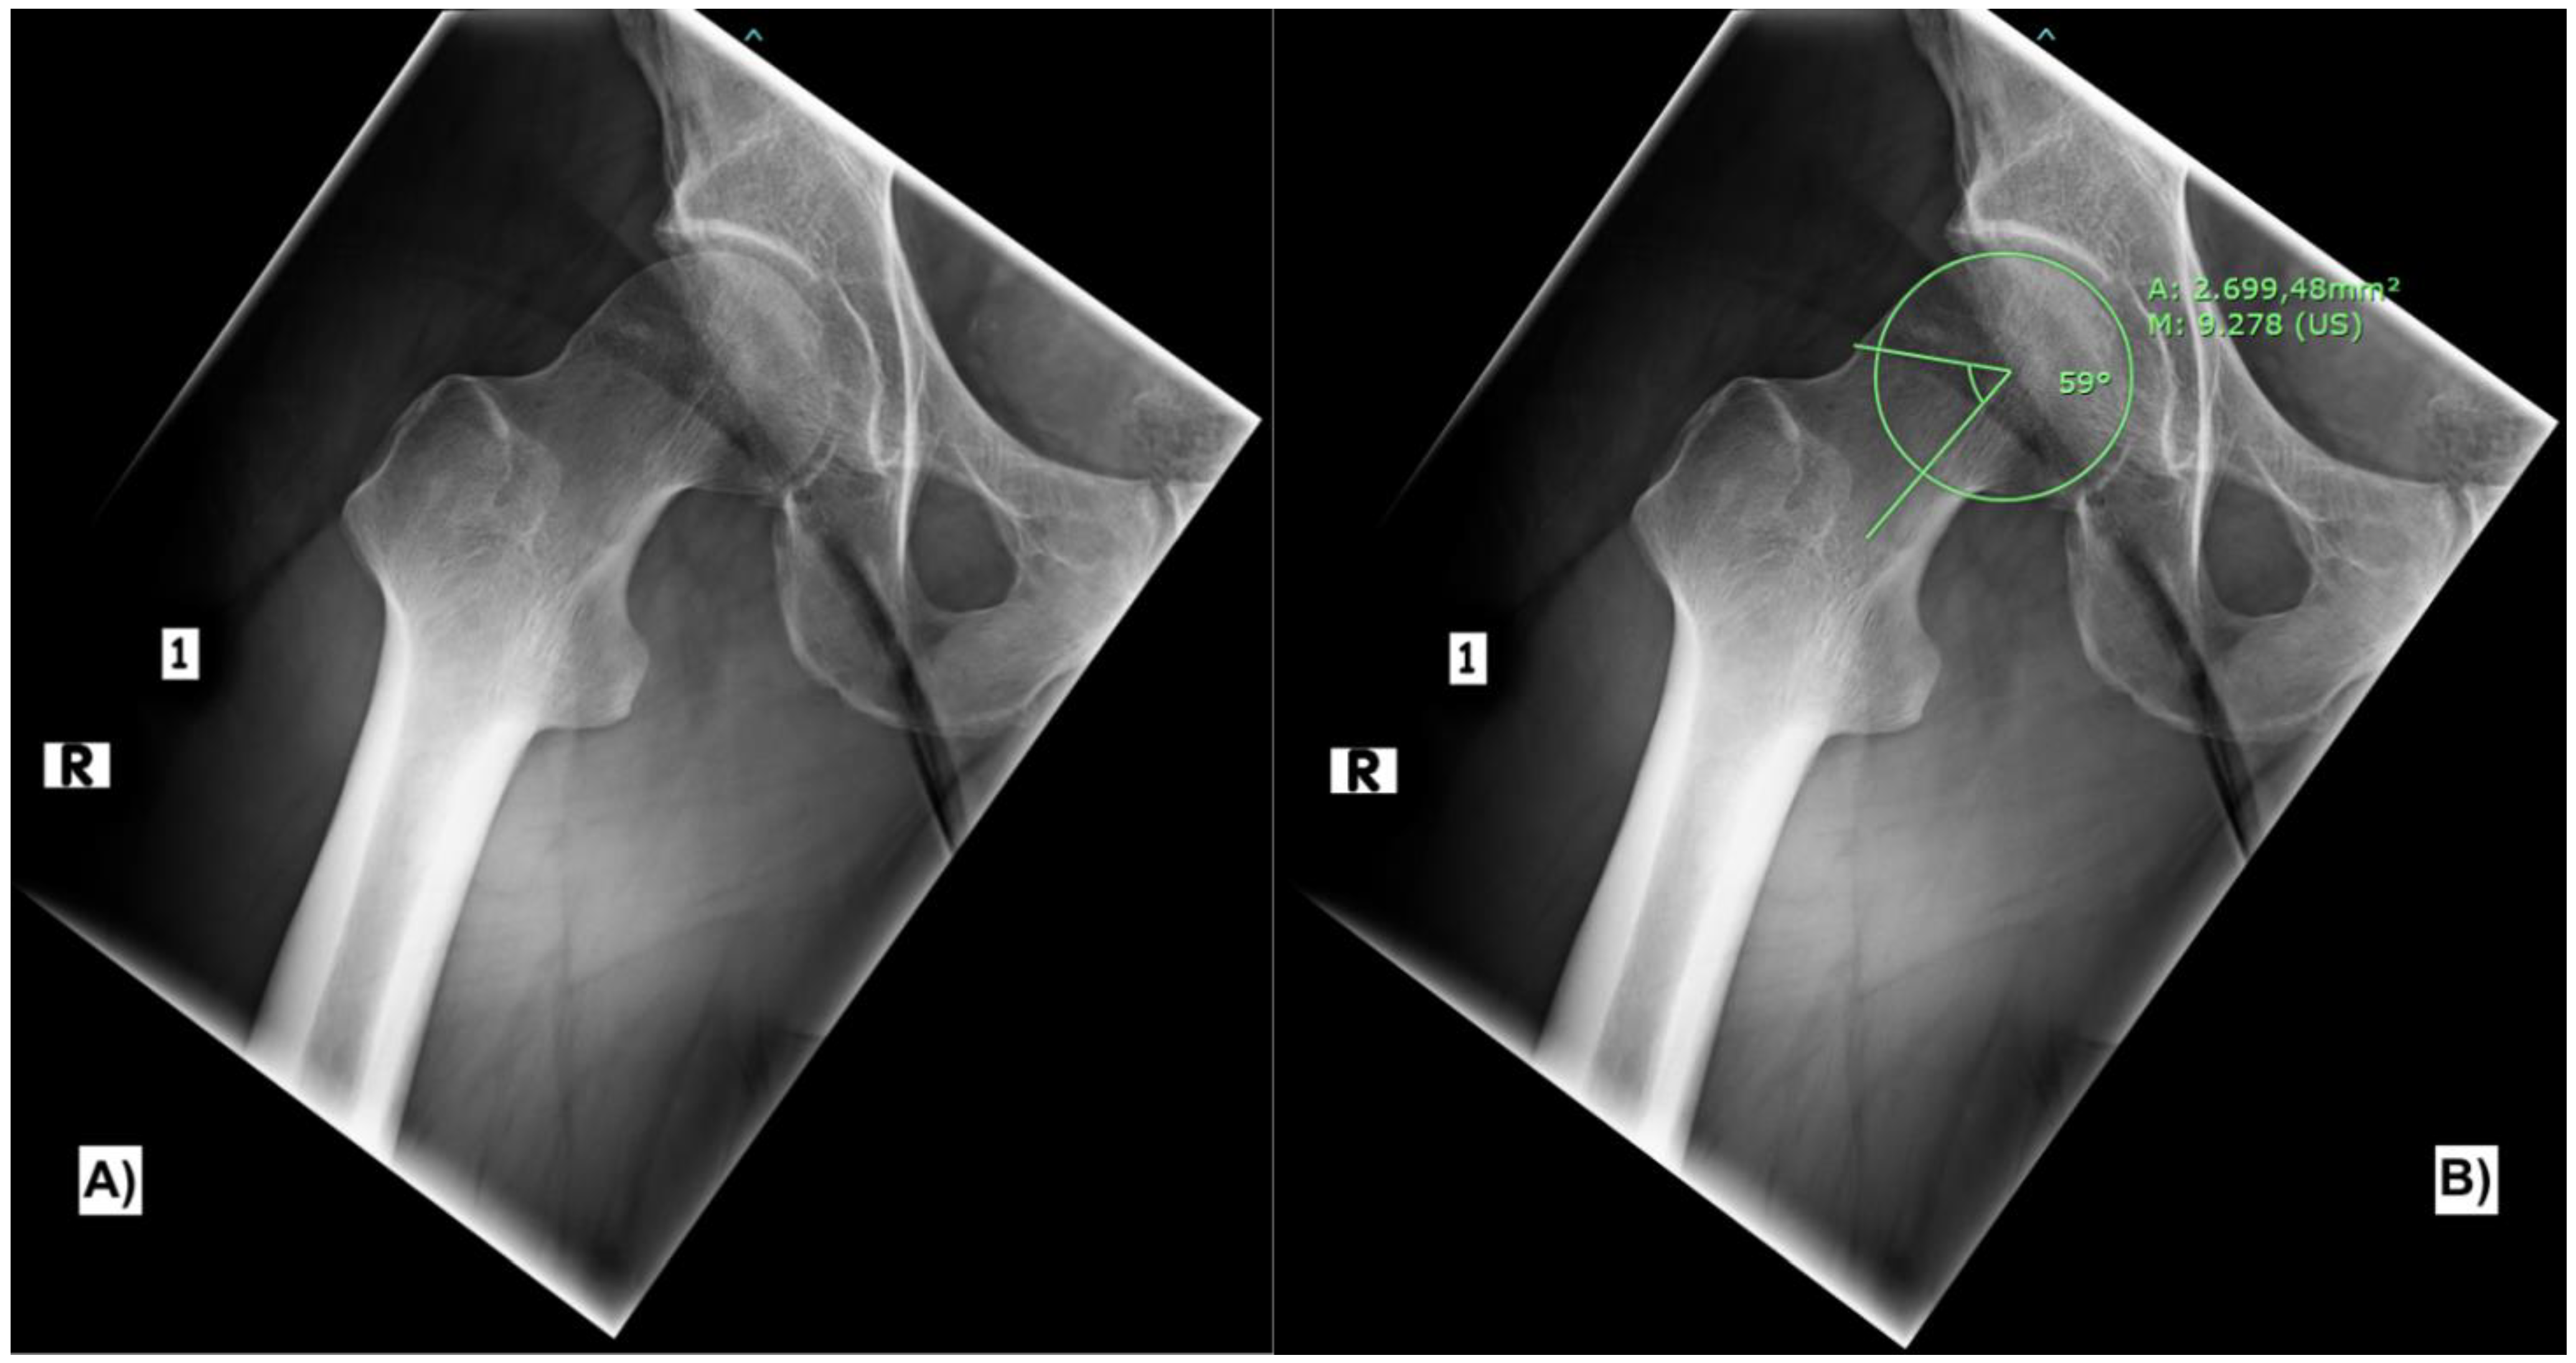

The main finding in the MRI was a localized collection of hematoma medial to the iliotibial band, between the iliotibial band and the greater trochanter (Figure 2). Compared to the left side, there was an increased distancing of the fascia lata or the iliotibial tract from the greater trochanter and a redundant, wavy cross-section of the fascia lata at the proximal thigh. Further, hematoma was also detected superficially, subcutaneously at the periphery of the iliotibial band and the gluteus maximus tendon. The insertion of the gluteus maximus muscle at the gluteal tuberosity of the femur was intact. Still, the insertion of the gluteus maximus tendon into the intermuscular septum was elevated and injured (Figure 2). Neither the gluteus medius nor the gluteus minimus tendons were injured. Also, the insertion of the quadratus femoris tendon and the insertion of the iliopsoas tendon at the lesser trochanter were intact. Some fluid was surrounding the tensor fasciae latae muscle. Otherwise, inconspicuous internal signals around the adductors and hip flexors were noticed.

Figure 2. Axial FRFSE PD sequence (A) showing collection of hematoma medial to the iliotibial band with disruption of the superficial insertion of the gluteus maximus muscle at the iliotibial band and intermuscular septum (Arrow). The injury is again demonstrated in coronal STIR sequence (B).